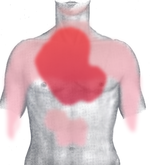

Rough diagram of pain zones in myocardial infarction (dark red = most typical area, light red = other possible areas, view of the chest).

Back view.

يسبب احتشاء العضلة القلبية وهو ألم حاد في منتصف الصدر يوصف بأنه عاصر أو طاعن أو ضاغط أو ضيق شديد بالصدر وهو يماثل ألم الخناق الصدري ولكنه يتميز عنه ب

الألم يمتد عادة إلى الذراع الأيسر ولكنه قد يمتد إلى الرقبة والفك السفلي الكتف الذراع الأيمن الظهر أو الشرسوف يترافق مع أعراض التعرق الشديد البرودة الخفقان الغثيان الإقياء أو الشعور بالدوار